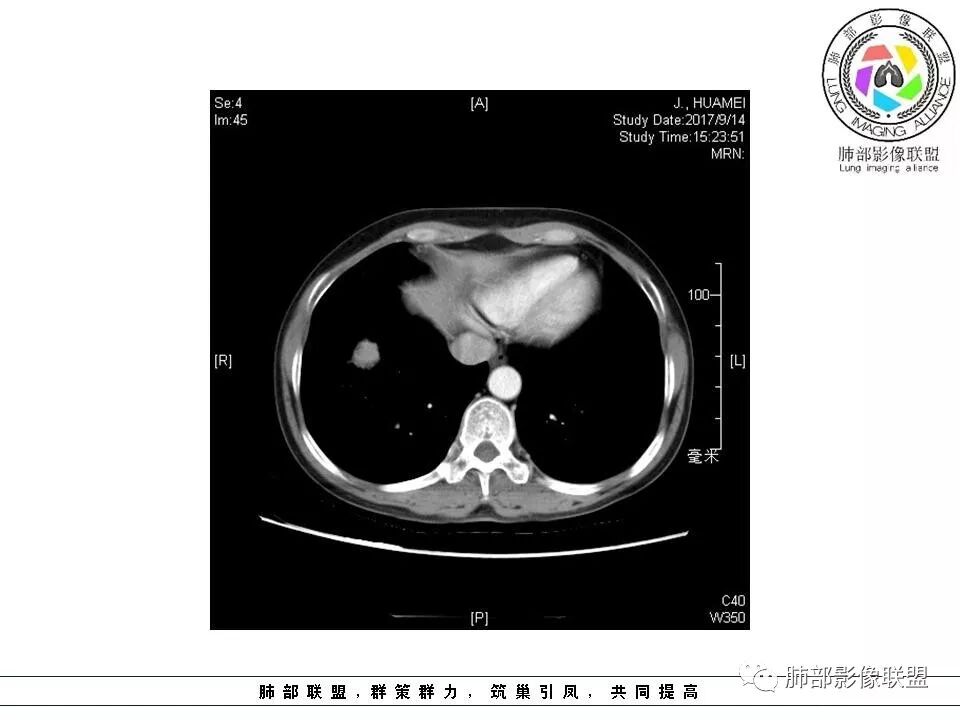

晨读:右肺下叶肿块影,浅分叶,不均匀强化,有血管穿行其中,考虑肺癌,神经内分泌肿瘤可能性大。

右肺下叶结节,边缘毛糙,内支气管推移,有血管贴行,小细胞肺癌?

晨读:右下肺前基底段支气管亚段分叉处占位,密度均匀、中度均匀强化,结节近边缘有支气管、血管穿行,结节边缘较光滑、有细短毛刺、无分叶,结节周围无卫星灶。考虑:PSP,鉴别:小细胞肺癌、不典型错钩瘤

内部支气管扩张,穿行血管形态自然,支持malt。

轻度分叶,支气管穿行,轻中度强化,血管漂浮,考虑MALT

右肺下叶前基底段肿块,边缘不光滑,毛糙,内见充气支气管征,边缘有浅分叶,肿块周围无病灶,排除了结核。增强扫描明显强化,内见血管影,考虑恶性肿瘤。女性,腺癌多见。

淋巴瘤与小细胞癌鉴别,纵隔内没有肿大淋巴结、结节边缘比较毛糙,淋巴瘤放第一位。

病灶呈圆形,轻度分叶,内见血管及支气管影,考虑MALT。

右肺下叶前基底段结节 边缘磨玻璃密度较清 内部支气管扩张,轻中度强化 穿行血管形态自然,支持淋巴瘤。

晨读:右肺下叶肿块影,浅分叶,边界清,轻度均匀强化,血管自然穿行,NSE偏高,考虑小细胞肺癌!

中年女性,右肺下叶前基底段肿块,轻度分叶,有棘样突出,充气支气管征穿行并形成脐凹征。增强扫描中度强化,内见血管影,血管壁毛糙,考虑恶性,腺癌?小细胞肺癌?

晨读,右肺下叶前基底段实性结节,边缘膨隆,可见多发浅分叶,结节内密度均匀,增强后呈轻度均匀强化,血管穿行走形自然,首先考虑恶性肿瘤,内有支气管穿行,淋巴瘤可能大,腺癌待排。

右肺下叶肿块,边缘光滑,浅分叶,膨隆明显,局部有清楚的ggo,考虑恶性,类癌首可能,鉴别腺,PSP。

中年女性,右下类圆形肿块,部分膨胧,边缘浅分叶,脐凹,内见血管穿行,增强轻中度强化,叶间胸膜结节?考虑腺癌,内有支气管穿行,鉴别淋巴瘤。

右肺下叶肿块影,边缘光滑,彭隆,浅分叶,内见支气管通过,增强明显强化,内见血管影,考虑恶性肿瘤,神经内分泌癌,鉴别淋巴瘤。

中年女性,体检发现,病史及化验无特殊。胸部CT右肺下叶前基底段见一类圆形结节,边界清楚,分叶不明显,边缘呈锯齿状改变,病灶内支气管穿行,无扩张及扭曲,增强扫描病灶明显均匀强化,内见穿行血管影,走形无扭曲。考虑粘膜相关性淋巴瘤可能。鉴别炎性假瘤、腺癌及小细胞癌。

胸CT:右肺下叶前基底段占位性病变,内可见支气管穿过,病灶边缘不规则,呈浅分叶,未见明显毛刺。纵隔窗可见病灶密度相对均匀,增强可见病灶强化,内可见血管增粗,边缘模糊,总体考虑恶性,腺?。良性疾病鉴别错构。

右下肺类圆形实形结节,边缘膨隆,浅分叶,其内可见支气管及血管影走行,轻度强化,考虑恶性病灶,淋巴瘤?类癌?

边缘彭隆,还是考虑肿瘤,支气管通入,肺内原发,支气管自然穿行稍扩张,血管比较自然同行,漂浮征,增强后整个比较均匀无明显坏死,淋巴瘤首选。恶性应该没有问题,建议穿刺。

这个病灶边缘还是有一点点恶性征象,有分叶,似乎有点地方还有一些小毛刺样感觉

部分区域整体以膨隆为主,部分区域稍收缩

内部支气管走形非常自然,达远端稍扩张;内部血管穿行也非常自然

内部密度比较均匀,我们一般来说,首先良性肿瘤不支持,因为它里面的血管走形太自然了;然后就是炎性病变跟恶性肿瘤,但是它的边缘膨隆比较厉害,有些地方还毛刺,不是很清楚,倾向一个恶性病变

恶性的血管穿行自然,包括支气管稍扩张,最常见还是淋巴瘤,它强化比较均匀;

粘液腺癌一般支气管扩张比较罕见,这个密度及强化太均匀,不是很符合,所以把淋巴瘤放前面,癌待排;

方向定在恶性的,炎性病变不是很符合